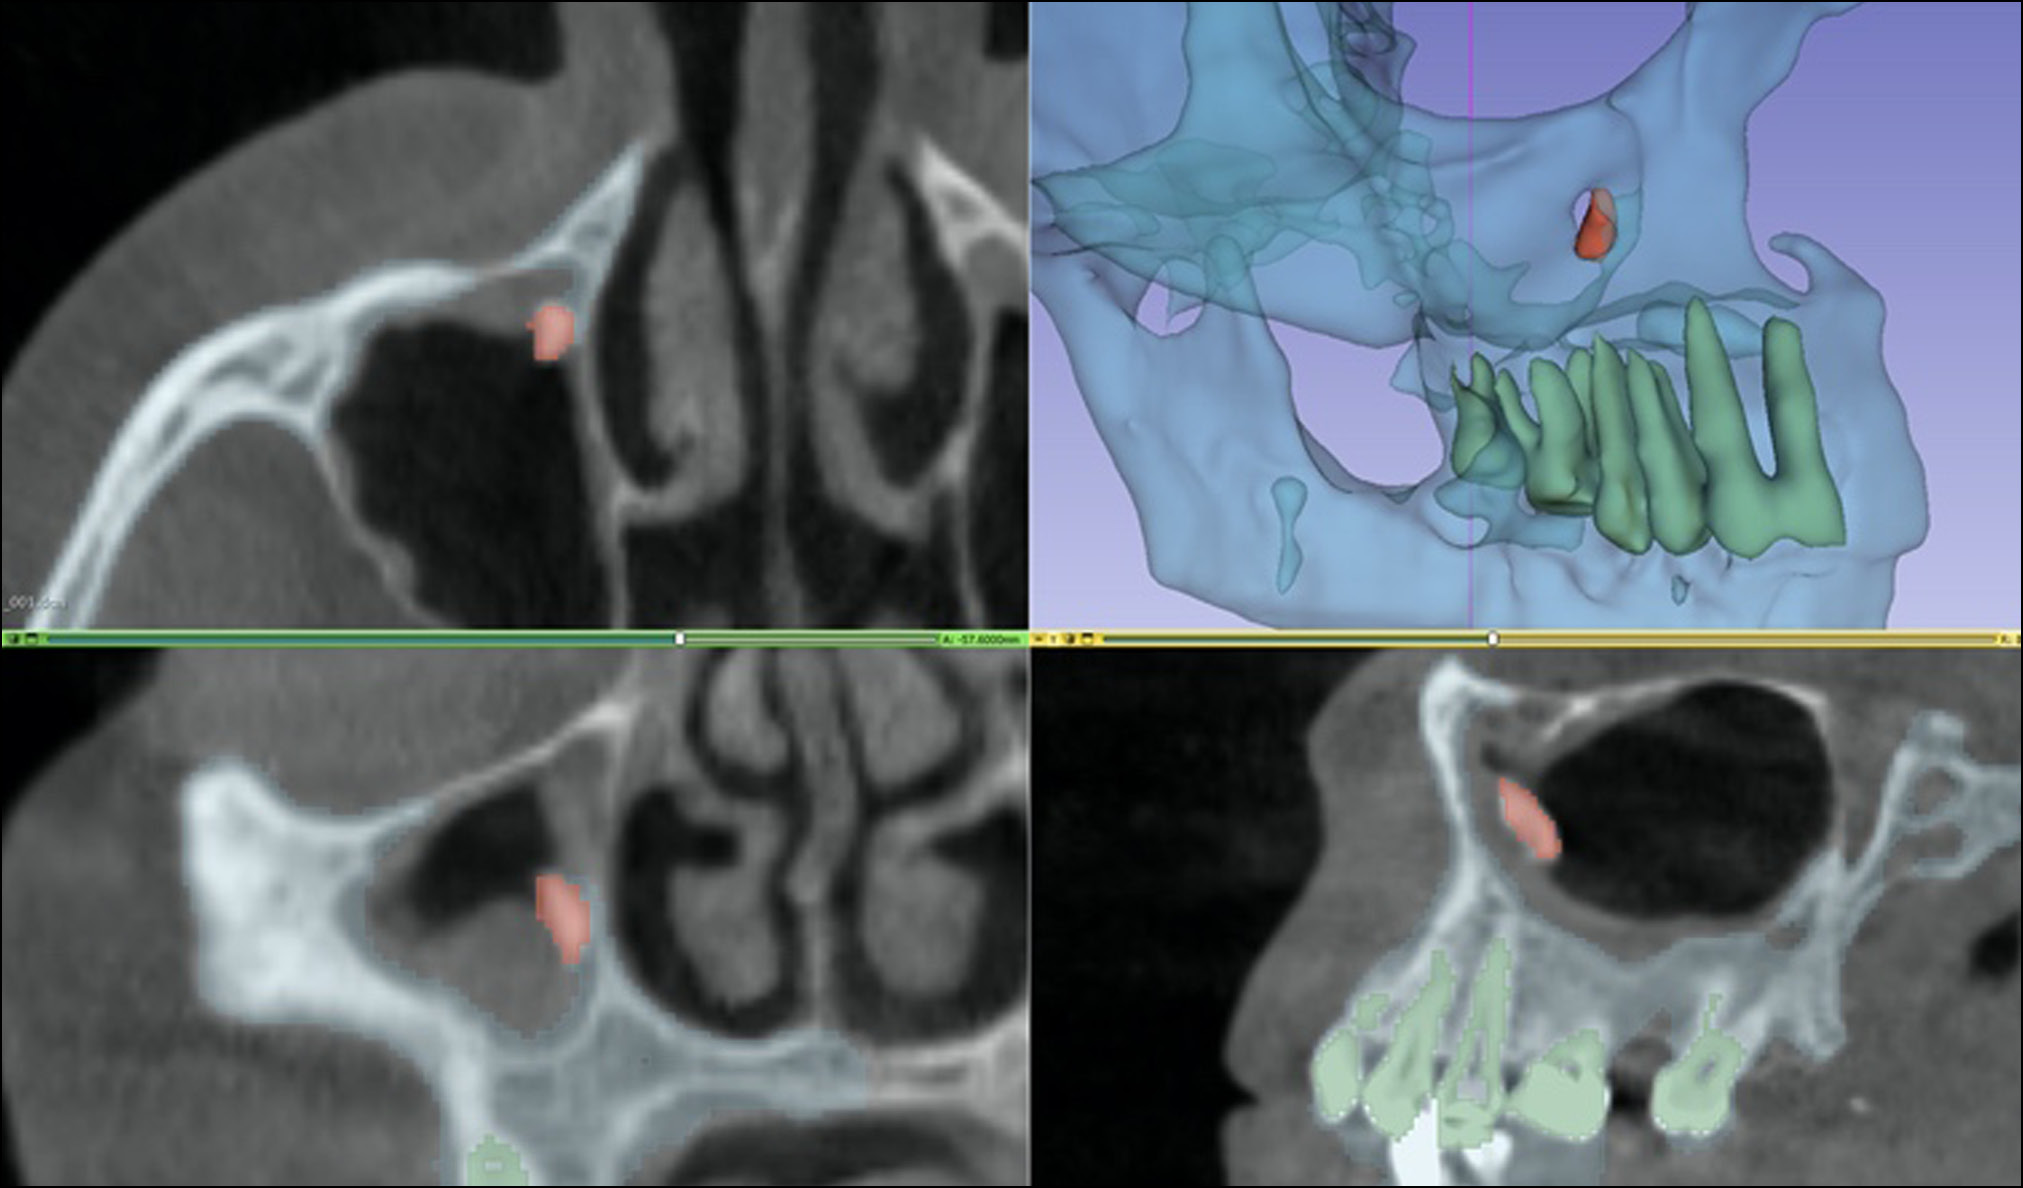

- Сегментация 3D-изображения зоны вмешательства (новообразования, кисты, зубы и инородные тела). Для сегментации изображений и создания 3D-моделей использовали специальное программное обеспечение Medgital Vision Editor, предназначенное для обработки медицинских 3D-изображений.

В программу загружали КЛКТ-изображения в формате DICOM и изображения, полученные методом оптического сканирования на предоперационном этапе. После совмещения DICOM- и STL-файлов хирург определял зону вмешательства и начинал построение 3D-проекции. Зона вмешательства представляет собой область, в которой локализованы новообразования, кисты или ретенированные зубы. В зоне вмешательства предусматривали достаточное расстояние до всех прилежащих анатомических структур, таких как нервы и корни зубов. Следующим шагом была сегментация зоны вмешательства. Сегментацию изображения выполняли вручную или полуавтоматически (рис. 13).

Рис. 13. Этап сегментации в программе Medgital Vision Editor (инородное тело в верхнечелюстной пазухе).

Полученный файл с сегментированной зоной вмешательства сохраняли в формате STL.